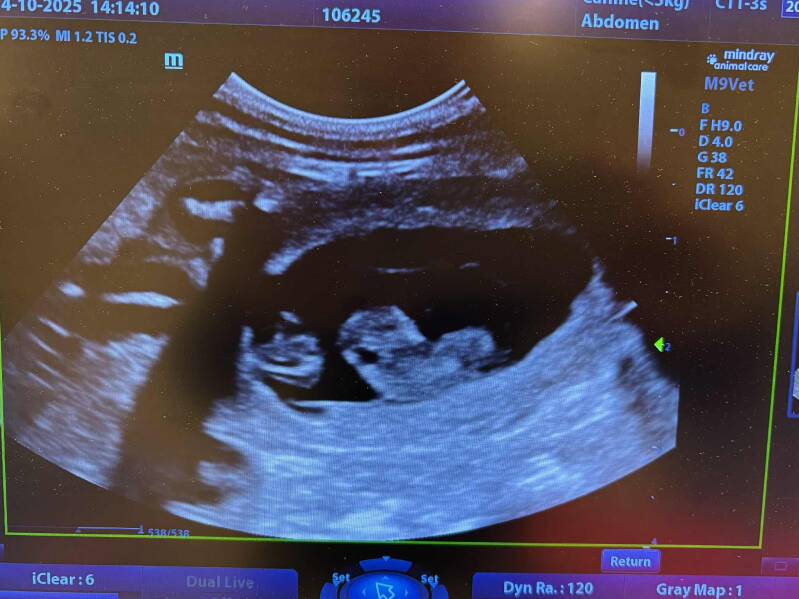

Star är nu parad med en mycket spännande kombo som avslöjas när vi vet om hon är dräktig. Jag väntar med stor spänning 😍